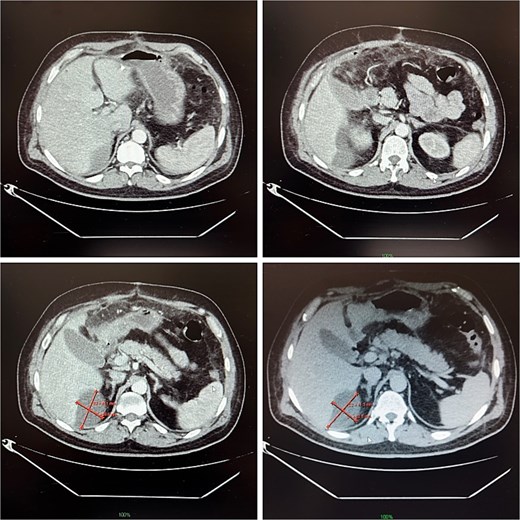

On postoperative day 14, the patient remained febrile. Computed tomography revealed a secondary abscess in segment VII (Fig. 2), which was successfully managed by percutaneous drainage under ultrasound guidance (Fig. 3). The regimen was subsequently switched to intravenous linezolid 600 mg twice daily, combined with antifungal therapy. The drains were gradually removed by postoperative day 30, while intravenous therapy continued until day 35. The patient was discharged on day 37.

Contrast-enhanced abdominal CT on postoperative day 14, demonstrating a 9 × 5 cm abscess in segment VII.